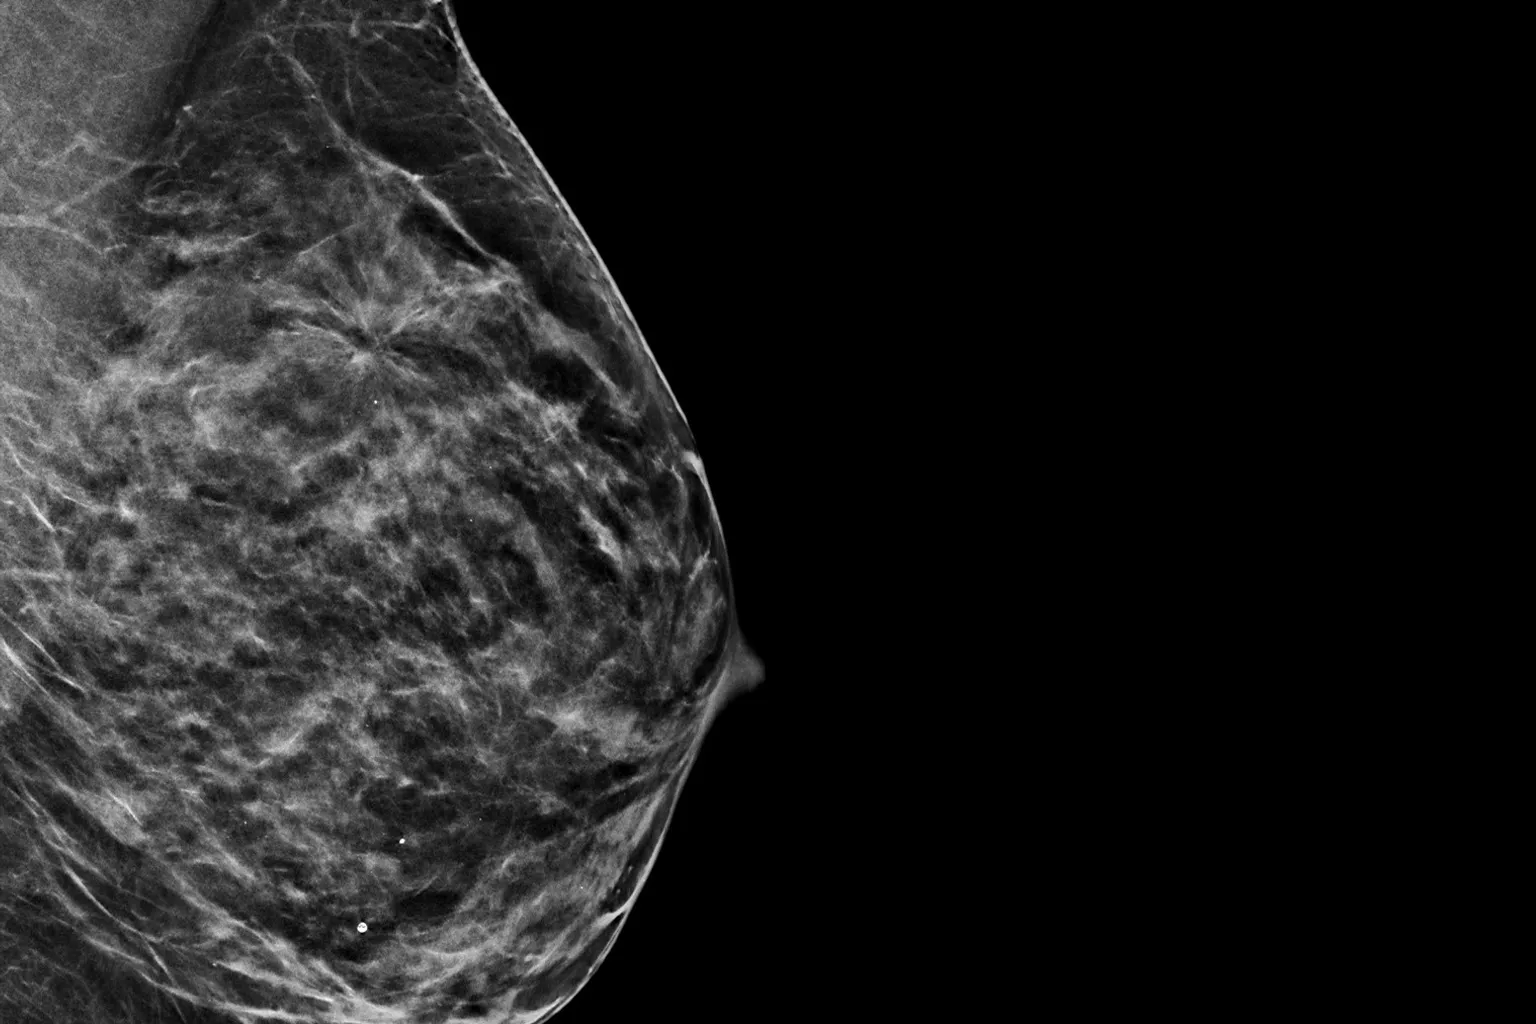

x-ray image of breast on black background

Raise your breast cancer screening performance1-4 with C-View software and instantly generated synthesised 2D images. It not only enhances details and speeds up the analysis, but also reduces radiation dose levels for your patients. C-View 2D images are clinically proven3,5 and FDA approved to diagnostically replace the FFDM images within a tomosynthesis screening exam.

Architectural distortions, mass lesions, and bright spots commonly found in microcalcifications are more visible in the C-View 2D image than on the traditional FFDM 2D images or tomo slices.4,6-9

Architectural distortions, mass lesions, and bright spots commonly found in microcalcifications, are more visible in the C-View 2D image than on the traditional FFDM 2D image or tomo slice.4,6-9